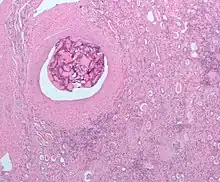

Les tumeurs hépatiques peuvent aussi bénéficier de cette modalité thérapeutique et il est même possible de réaliser dans ce cas une chimio-embolisation intra-artérielle. L'occlusion des artères nourricières par l'agent embolique est alors associée à l'injection intra-tumorale d'une chimiothérapie.